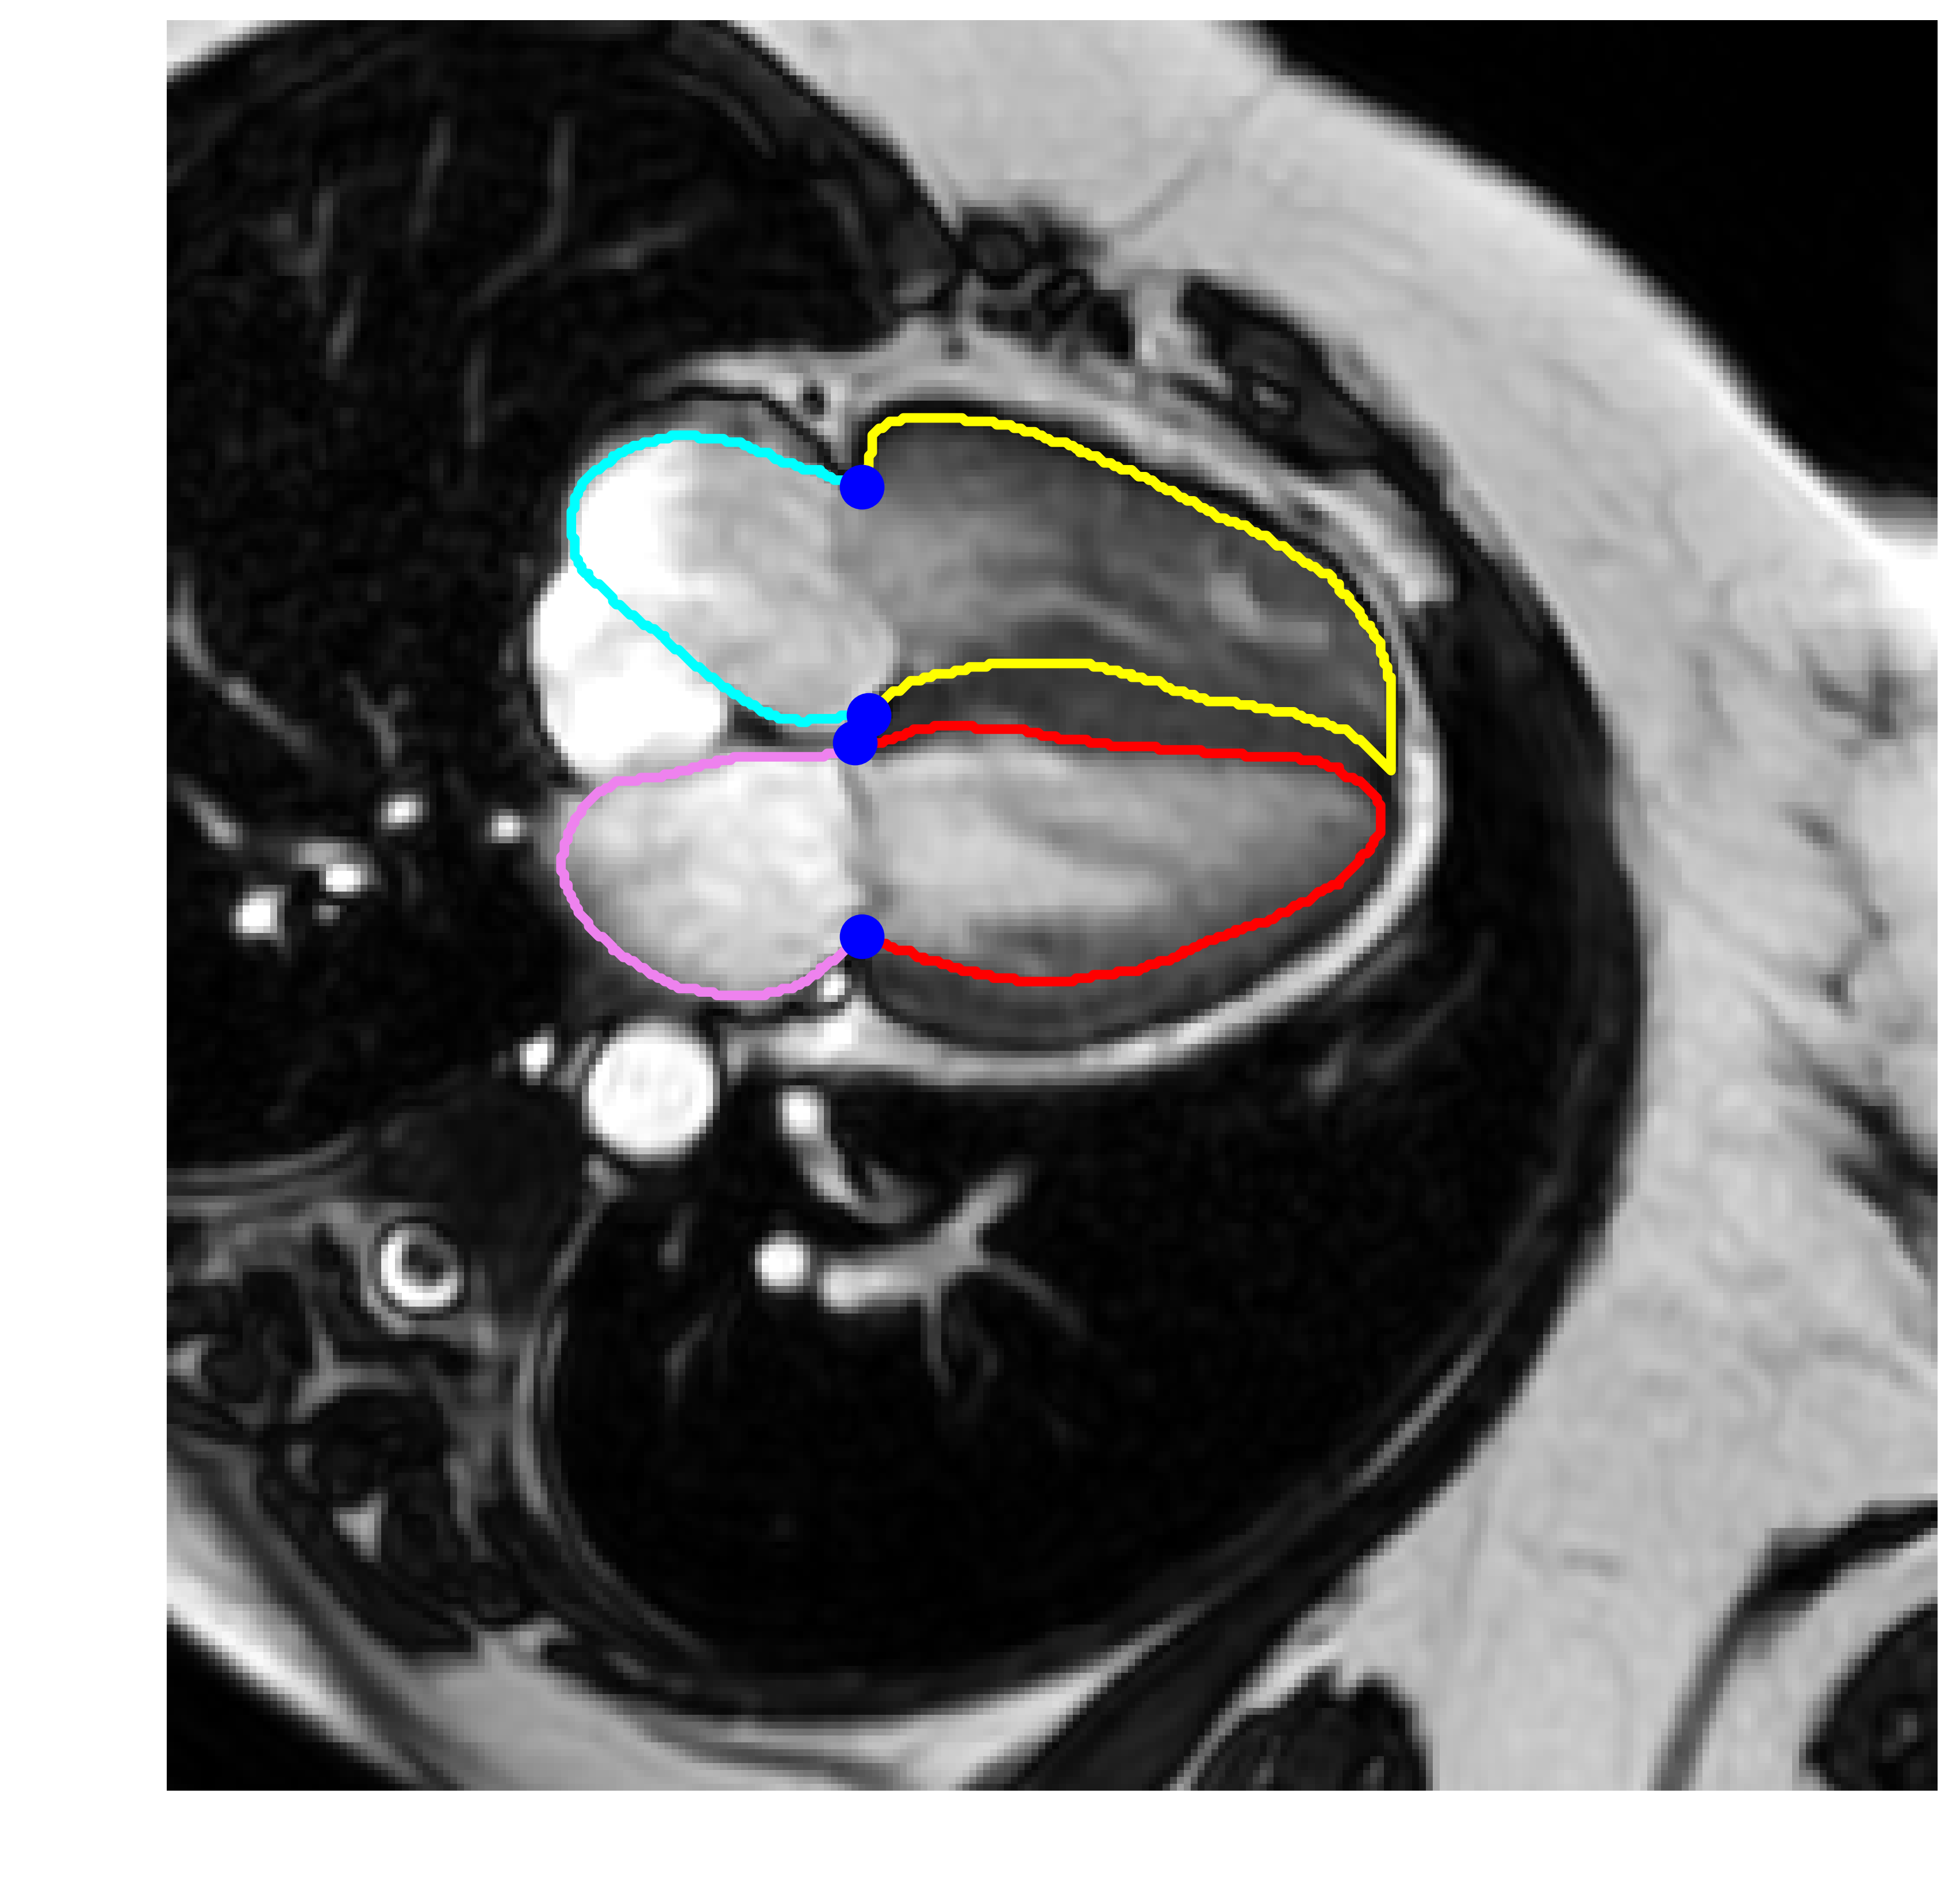

This study utilized a cohort of 374 subjects with 2D+t cine-MRI scans, with each subject having a 4-chamber long-axis (LAX) view. The scans were randomly selected from the ASPIRE registry [Hurdman et al., 2012], and were acquired using a balanced steady state free precession (bSSFP) sequence. The ASPIRE registry included patients with a wide range of pathologies including left heart disease (15%), lung disease (12%), chronic thromboembolic pulmonary arterial hypertension (PAH) (21%), PAH (29%), other PAH (2%) and non-PAH (21%). The scans were acquired using Siemens (n=41) and GE scanners (n=333). The dataset was split into 80% for training (n=300) and 20% for validation (n=74) scans. The training/validation split was stratified based on the scanner. Specifically, out of the 300 scans used for training, 33 scans were from Siemens, and 267 scans were from GE. For the validation set, consisting of 74 scans, 8 scans were from Siemens, and 66 scans were from GE. Expert manual contours for the left ventricle (LV), right ventricle (RV), LV myocardium (LVM), left atrium (LA) and right atrium (RA) were defined in all temporal frames by four observers with 2, 3, 11, and 13 years of CMR experience [Alandejani et al., 2022]. The number of frames per scan ranged from 20 to 30. Each scan corresponds to a complete cardiac cycle. The image series and corresponding contours were center-cropped and resampled into image stacks of size . These images maintain an in-plane resolution of mm, with a total of 25 time frames. The image stacks were normalized to have intensity values between [0, 1]. A total of four landmark points were defined based on the manual contours, these points represented the hinge points of the mitral and tricuspid valves as shown in Fig. 3. These anatomical locations represent the regions with the largest cardiac motion amplitude and are used for the evaluation of the GW registration. Figure 2 illustrates the diversity and variation present in the dataset, as seen through samples depicting a range of field of views, noise levels, contrasts, heart sizes, and orientations.

Figure 4 shows visual examples for the contours, DVF, and determinant of the Jacobian estimated from the proposed method. Figure 5 shows a visual comparison between elastix, Group-RegNet and proposed network against the manually defined contours. It shows that the proposed method achieves better results compared to the other methods especially at the landmark points.